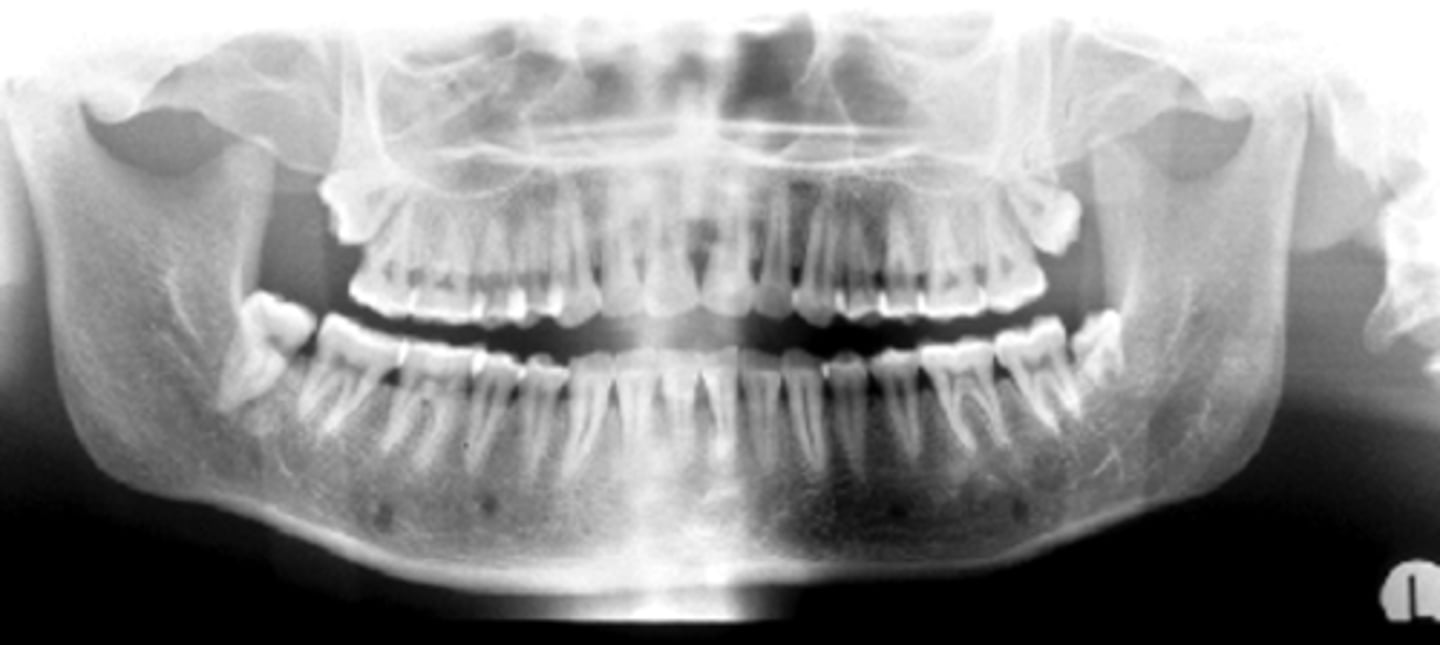

ID the positional error from the radiograph:

None - ideal